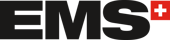

Horizontální augmentace alveolu pro zavedení implantátu.

Materiály a metody

Celkem patnáct pacientů bylo ošetřeno stejným lékařem v Godt Smil Odense od listopadu 2013 do března 2015. Devět pacientů bylo mužského a šest ženského pohlaví. Nejmladšímu pacientovi bylo dvacet šest let a nejstaršímu sedmdesát osm. U tě-

chto patnácti pacientů bylo zavedeno devatenáct alogenních kostních bloků za účelem horizontální augmentace atrofického alveolárního výběžku jak v dolní, tak v horní čelisti před zavedením implantátu. Všichni pacienti byli celkově zdrávi, jeden z nich byl kuřák. Pokud bylo třeba, podstoupili před chirurgickým zákrokem všichni pacienti parodontologickou léčbu.